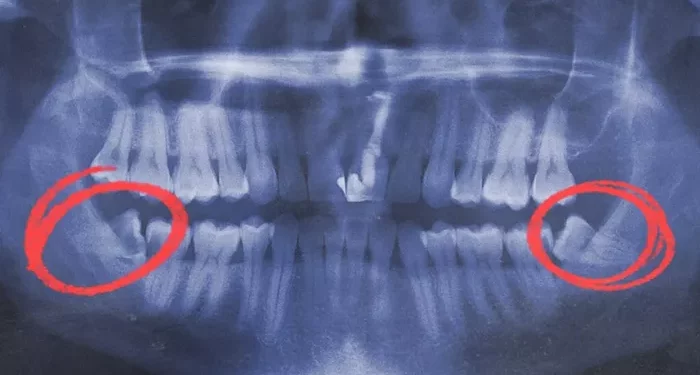

Wisdom teeth, also known as third molars, are the last teeth to erupt in the mouth. Due to the evolution of the human jaw, many people don’t have enough space for these teeth to erupt properly, leading to impacted wisdom teeth. Impacted wisdom teeth can cause a variety of problems, including pain, infection, damage to adjacent teeth, and even cysts or tumors. As a result, many dentists recommend removing wisdom teeth, especially if they’re impacted or causing issues.

The extraction process itself can vary depending on the position and condition of the wisdom teeth. Simple extractions involve removing teeth that have erupted fully or partially and are accessible. Surgical extractions, on the other hand, involve removing teeth that are impacted or buried beneath the gum line and bone. This typically requires more invasive techniques, including cutting through gum tissue and bone, and sometimes even sectioning the tooth into smaller pieces to make removal easier.